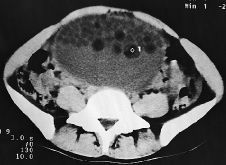

Teratoma quístico de ovario con bolas grasas intraquísticas. A propósito de un caso,

Ovarian cystic teratoma containing balls of fat. A case report,

Aurora Salinas, Manuela Rebolledo, Manuel Escribano, Juan P Alejo, José Moreno